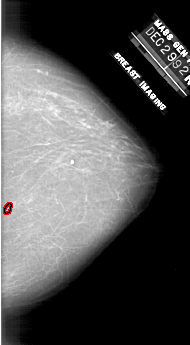

A_1910_1.RIGHT_CC

RIGHT_CC LINES 6196 PIXELS_PER_LINE 3406 BITS_PER_PIXEL 12 RESOLUTION 43.5 OVERLAY

FILE: A_1910_1.RIGHT_CC.OVERLAY

TOTAL_ABNORMALITIES 1

ABNORMALITY 1

LESION_TYPE CALCIFICATION TYPE PLEOMORPHIC DISTRIBUTION CLUSTERED

ASSESSMENT 4

SUBTLETY 3

PATHOLOGY BENIGN